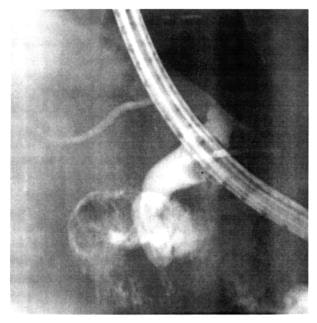

На фигуре 3:

фиг. 3

рентгенограмма «внепечёночных жёлчных протоков» и правого «внутрипечёночного протока» (выполненных предложенным «Способом рентгенологической визуализации …»).